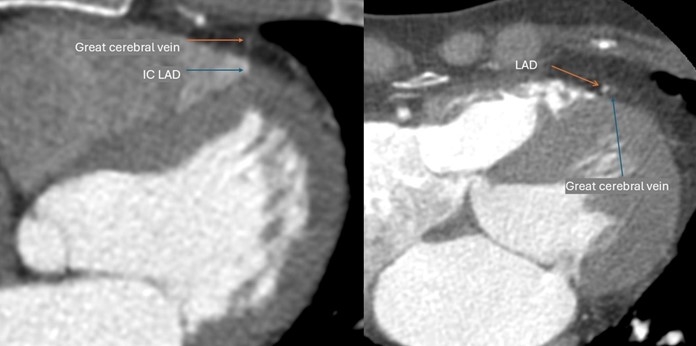

Case Summary: A female in her 30s presented with left-sided chest pain radiating to the left upper limb. ECG, echocardiography, and chest x-ray were normal. Given her age, non-smoking status, and angina-like presentation, she was referred for CT coronary angiography to look for any structural cardiac or coronary anomaly. CT showed no hemodynamically significant plaque. However, a variant course of LAD was noted, with 12 mm long and 1-2 mm deep MB affecting the mid-segment of LAD. MB continued as IC for 17 mm length along the mid-to-distal course of LAD in the right ventricular cavity between the free and septal walls of the chamber. Long-segment mild-to-moderate stenosis was noted in the affected segments (MB and IC) on diastolic reconstruction with mild pre- and post-stenotic dilatation of LAD.

IC is difficult to recognize in conventional angiography. We noticed two important imaging features in this case that can act as clues for the identification of this variant on conventional angiography. One was a subtle secondary curve noted at the level of IC. The other was a relatively posterior position of LAD with respect to the great cerebral vein and a demonstrable increased distance between them. The patient was managed medically and counseled in cardiology.